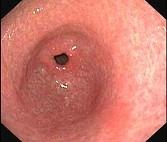

问题 女,54岁,腹胀、嗳气4个月余,无腹痛、反酸、恶心、呕吐,一般情况良好,二便正常,查体无异。B超肝胆无异常,胃镜检查如图,最有可能性的诊断是 ( )

选项 A.神经性嗳气 B.消化性溃疡 C.慢性胃炎 D.慢性胰腺炎 E.胃癌

答案 A